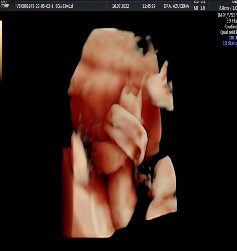

Se evidencia la presencia del signo de la soga colgante. En un corte transversal, se observa al cordón umbilical enrollado sobre sí mismo (Figura 2), formando un lazo y un bucle fijo, con un nudo que configura un lazo en el cordón umbilical, lo que sugiere la posibilidad de un nudo verdadero. Tras la aplicación Doppler color e imágenes 3D, se corroboró la sospecha diagnóstica (Figura 3).